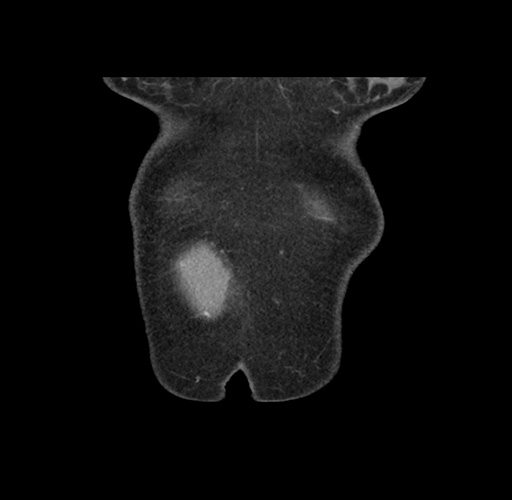

Imaging Analysis

Look through the patient's CT scan to identify any areas of concern for the necessary procedure.

Based on your CT findings, which issue(s) would give reason for "planned slowing down moment(s)" in this case?

Considering a standard left lateral sectionectomy procedure, what step(s) of the operation would you do differently in this case ?